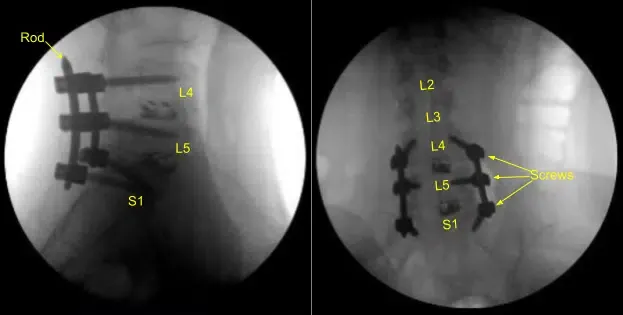

Se obtuvo una tomografía computarizada intraoperatoria, los datos se transfirieron al ordenador de neuronavegación y se verificó la precisión. Se utilizaron técnicas de neuronavegación para canular el primer segmento sacro derecho que luego se palpaba en busca de rupturas y se medía a una profundidad de 35 mm. Se utilizaba un tapón de 6,0 mm para enhebrar la canulación. De nuevo se palpó para detectar brechas y se colocó un tornillo pedicular de titanio de 7,5 x 35 mm con buen sujeito óseo y firmeza.

A continuación, se volvió a colocar el drapado al paciente y se realizó una segunda tomografía computarizada intraoperatoria que mostró la correcta posición de este tornillo pedicular. Las señales de neuromonitorización se mantuvieron estables en todo momento. A continuación, el proceso transversal L5-S1 y ala fueron decorificados con un taladro de alta velocidad para la artrodesis tras explorar la fusión y no identificar la artrodesis ósea ni el injerto óseo.

La pequeña dehiscencia en la incisión del lado izquierdo fue desbridada y la piel se volvió a cerrar. Todas las incisiones se limpiaron y secaron de forma estéril, y los apósitos se aplicaron de forma estéril. Se aplicó un recipiente Hemovac con succión. La unidad C-arm se cubría de forma estéril y se utilizaba para la confirmación por AP y fluoroscopia lateral del correcto hardware y la posición de la instrumentación, específicamente la colocación de las varillas.